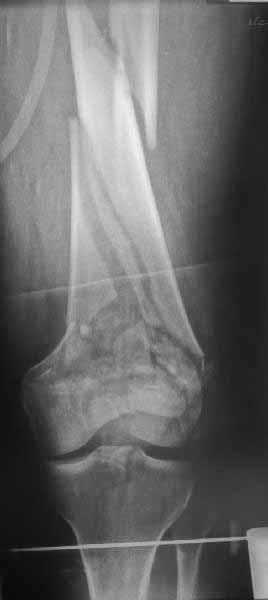

В приложении пример недавней операции, C3, открытая репозиция, фиксация мыщелков спицами и винтами, ретроградный синтез большеберцовым гвоздем 10,5 мм диаметром, винты 5 мм.

Позволю себе напомнить коллегам ещё раз, что являюсь сторонником антеградного остеосинтеза при переломах дистального эпиметафиза бедренной кости. Такая приверженность основана не на преимуществах внесуставного введения стержня или большем проценте положительных результатов. Она основана на возможности обеспечить блокирование на минимальном расстоянии от суставной поверхности в нескомпрометированной кости и, таким образом стабилизировать максимально низкие переломы. В приведенном Вами случае самый дистальный из блокирующих винтов проведен на расстоянии более 2 см от конца стержня. Из-за того, что к стержню присоединяется кондуктор, на стержне теряется 1-1,5 см его длины, где можно было разместить отверстия для блокирования. И что более важно, вместе с потерянной для этой цели длиной стержня утрачивается для размещения блокировочных винтов, пожалуй, самая ценная часть дистального эпиметафиза бедренной кости. Проблемы дистального блокирования в разных плоскостях, локализации точки ввода стержня при антеградном остеосинтезе – это всё решаемые технические проблемы. Но антеградный остеосинтез низких дистальных переломов бедра при адекватном блокировании в нескомпрометированной кости обеспечивает решение стратегической задачи – стабильный остеосинтез и возможность нагрузки.

В приведенном Вами случае самый дистальный из блокирующих винтов проведен на расстоянии более 2 см от конца стержня.

На этом большеберцовом стержне центр ближайшего к кондуктору отверстия в 14 мм от конца. И пример был про то, что пластина тут, скорее всего, была бы не худшим выбором.